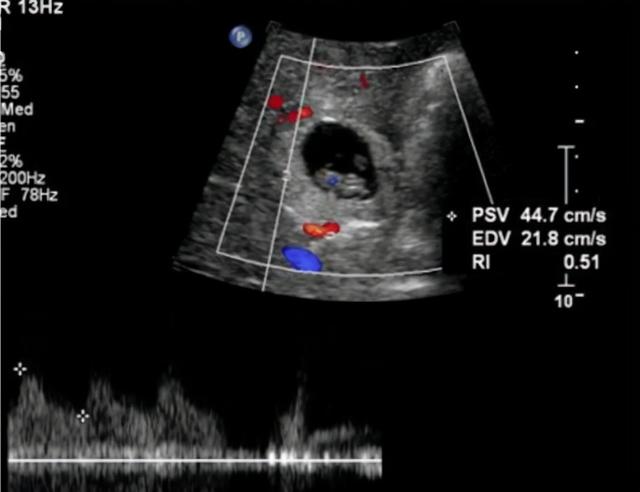

这位女士因为长时间没有来月经,肚子痛得难以忍受,去医院检查。然而,她没想到自己怀孕了,但胎儿不是在子宫里,而是在肝脏里。

总之,这个女人原来是一个极其罕见的“肝妊娠”,世界上病例不到30例,其中中国发现了6例。

一个例子发生在2016年。当时住在广西田东县的一位妇女,因为突然停经三个多月,去医院检查,才发现自己已经怀孕了。然而,子宫里没有孩子,但肝脏里有一个发育了三个多月的胎儿。

说白了,肝妊娠就是一种“宫外孕”。简单来说就是宫外孕。然而,肝脏妊娠是最罕见的异位妊娠之一。毕竟没人能想到胎儿还能出现在肝脏里,成为“心上人”。

对此,研究认为,受精卵由于输卵管畸形或炎症,不能成功进入子宫,因此会落在子宫外,在某些特殊情况下,甚至会跑进肝脏,肝脏会被视为子宫,在内部发育。

而且,受精卵植入肝脏后,仍然可以像子宫一样持续吸收营养,然后不断发育。但是,因为肝脏毕竟和子宫不同,如果不及时发现,可以让胎儿在肝脏发育,当胎儿4-5个月大时,肝脏就会破裂。

所以从这里也可以看出,肝脏妊娠的胎儿是不可能出生的。这种情况下,就要尽快终止妊娠,取出肝内胎儿,否则后果会很严重。